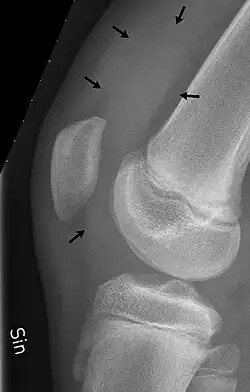

As bursas do joelho são sacos cheios de líquido e bolsas sinoviais que circundam a cavidade da articulação do joelho. As bursas têm paredes finas e são preenchidas com líquido sinovial . Eles representam o ponto fraco da articulação, mas também fornecem ampliações para o espaço articular.[1] Elas podem ser agrupadas em bursas comunicantes e não comunicantes ou, conforme sua localização - frontal, lateral ou medial.

- a bursa suprapatelar ou recesso entre a superfície anterior da parte inferior do fêmur e a superfície profunda do quadríceps femoral.[2] Ela permite o movimento do tendão do quadríceps sobre a extremidade distal do fêmur. Em cerca de 85% dos indivíduos, essa bursa se comunica com a articulação do joelho. A distensão desta bursa é geralmente uma indicação de derrame no joelho .[3]